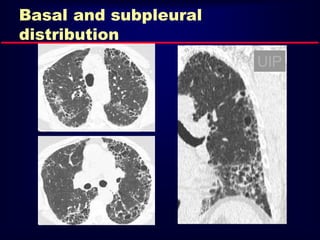

Basal and subpleural predominance

Basal and subpleural

distribution

UIP

Usual Interstitial Pneumonia UIP HRCTFindings Reticular opacities, thickened intra- and interlobular septa Irregular interfaces Honey combing and parenchymal distorsion Ground glass opacities (never prominent) Basal and subpleural predominance

• 97.